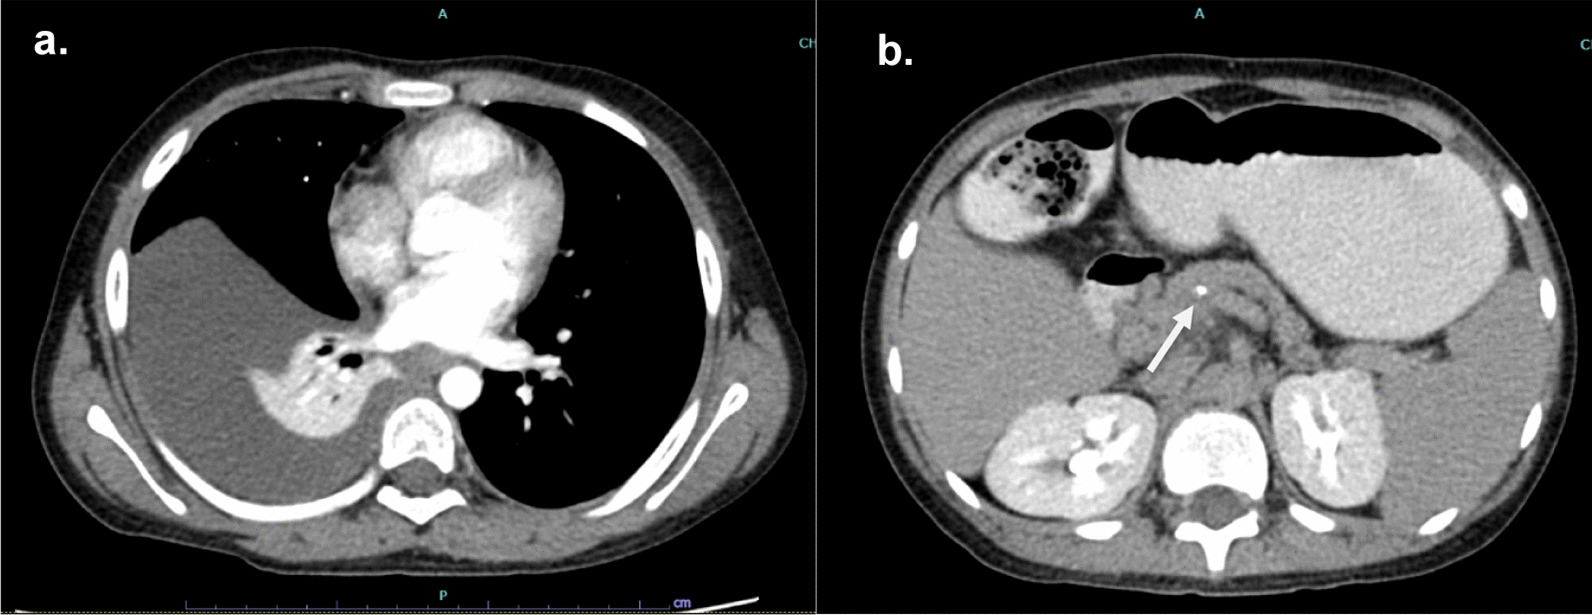

A 9-year-old boy was referred to Siriraj Hospital with recurrent abdominal pain and a three-week history of breathing difficulty. His first episode of abdominal pain appeared eight months prior and the symptoms were worsening. The patient had a normal perinatal history, developmentally age appropriate, and a negative family history of chronic pancreatitis. His height was 139 cm (75th percentile) and his weight was 28 kg (50th percentile). He was taken to the primary care hospital because he had fever and dyspnea for two days. Physical examination found a decrease in breath sounds at the right lung with dullness on percussion and mild tenderness at the epigastrium. Chest radiography showed massive right pleural effusion. The pleural fluid analysis revealed an exudative pattern with leukocytes count of 5,900 cell/L (70% neutrophil) and protein of 5.1 g/dL (serum protein 7.2 g/dL). A CT of the chest was sent to confirm massive right pleural effusion and to define the associated pathology but calcification of the pancreatic parenchyma suggestive of CP was accidentally found (Fig. 1). Further investigation of CP, serum amylase and lipase were 411 U/L and 532 U/L, respectively. Calcium, triglycerides, and blood sugar were normal. The patient was referred to our hospital for evaluation and treatment.

Fig. 1.

Initial CT scan reveals a pleural effusion and b calcification in the head of pancreas with dilatation of pancreatic duct (arrow)